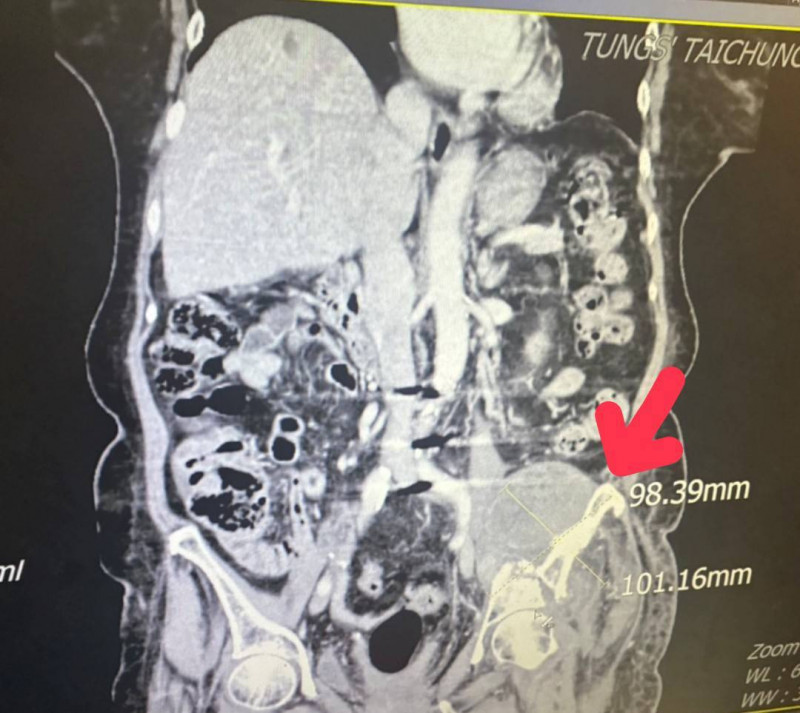

由於張婦的腫瘤細胞太大(約12.1公分x17.4公分),且腫瘤位置執行手術風險過高,葉啟源採用銳視刀適應性放射治療,利用空間分割點狀治療方式, 局部給予點狀高劑量的放射線,以高劑量消融巨大、抗放射性腫瘤,再配合傳統銳視刀,即以傳統劑量梯度保護周圍的健康組織與器官,經過1個月26次治療後,腫瘤縮小至9.8公分x10.1公分,緩解骶叢神經受壓迫的情況,疼痛明顯改善,也改善患者的行動能力。